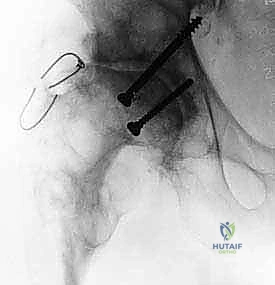

- التقييم السريري الشامل: يتم أخذ تاريخ مرضي مفصل، وفحص المريض سريرياً لتقييم نطاق الحركة، قوة العضلات، تفاوت طول الساقين، ومكان الألم بدقة.

- استبعاد العدوى (Infection Rule-out): لا يمكن إجراء مراجعة بمفصل دائم إذا كانت هناك عدوى بكتيرية نشطة. يطلب الدكتور هطيف تحاليل دم دقيقة (ESR, CRP) وفي كثير من الأحيان يقوم بسحب سائل من المفصل (Joint Aspiration) لتحليله زراعياً.

- التصوير الإشعاعي المتقدم: يتم إجراء صور أشعة سينية (X-rays) بوضعيات متعددة، بالإضافة إلى الأشعة المقطعية ثلاثية الأبعاد (3D CT Scan) مع تقنية تقليل انعكاس المعادن (MARS). هذا يسمح للدكتور هطيف برؤية حجم التجاويف العظمية بدقة مليمترية.

- التخطيط الرقمي (Digital Templating): باستخدام برامج حاسوبية متقدمة، يقوم الدكتور هطيف بتجربة أحجام وأشكال مختلفة من السيقان المخددة افتراضياً على أشعة المريض قبل دخول غرفة العمليات، مما يقلل من المفاجآت ويختصر وقت الجراحة.